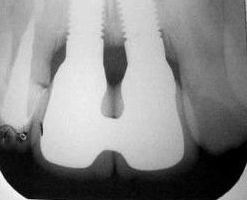

| RX periapical da zona traumatizada |

RX periapical da mesma região após a instalação dos implantes: 22/01/2004 |